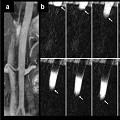

Dynamic quantitative nonenhanced magnetic resonance angiography of the abdominal aorta and lower extremities using cine fast interrupted steady-state in combination with arterial spin labeling: a feasibility study

Emily A. Aherne, et al.

Published on: 2 September 2019